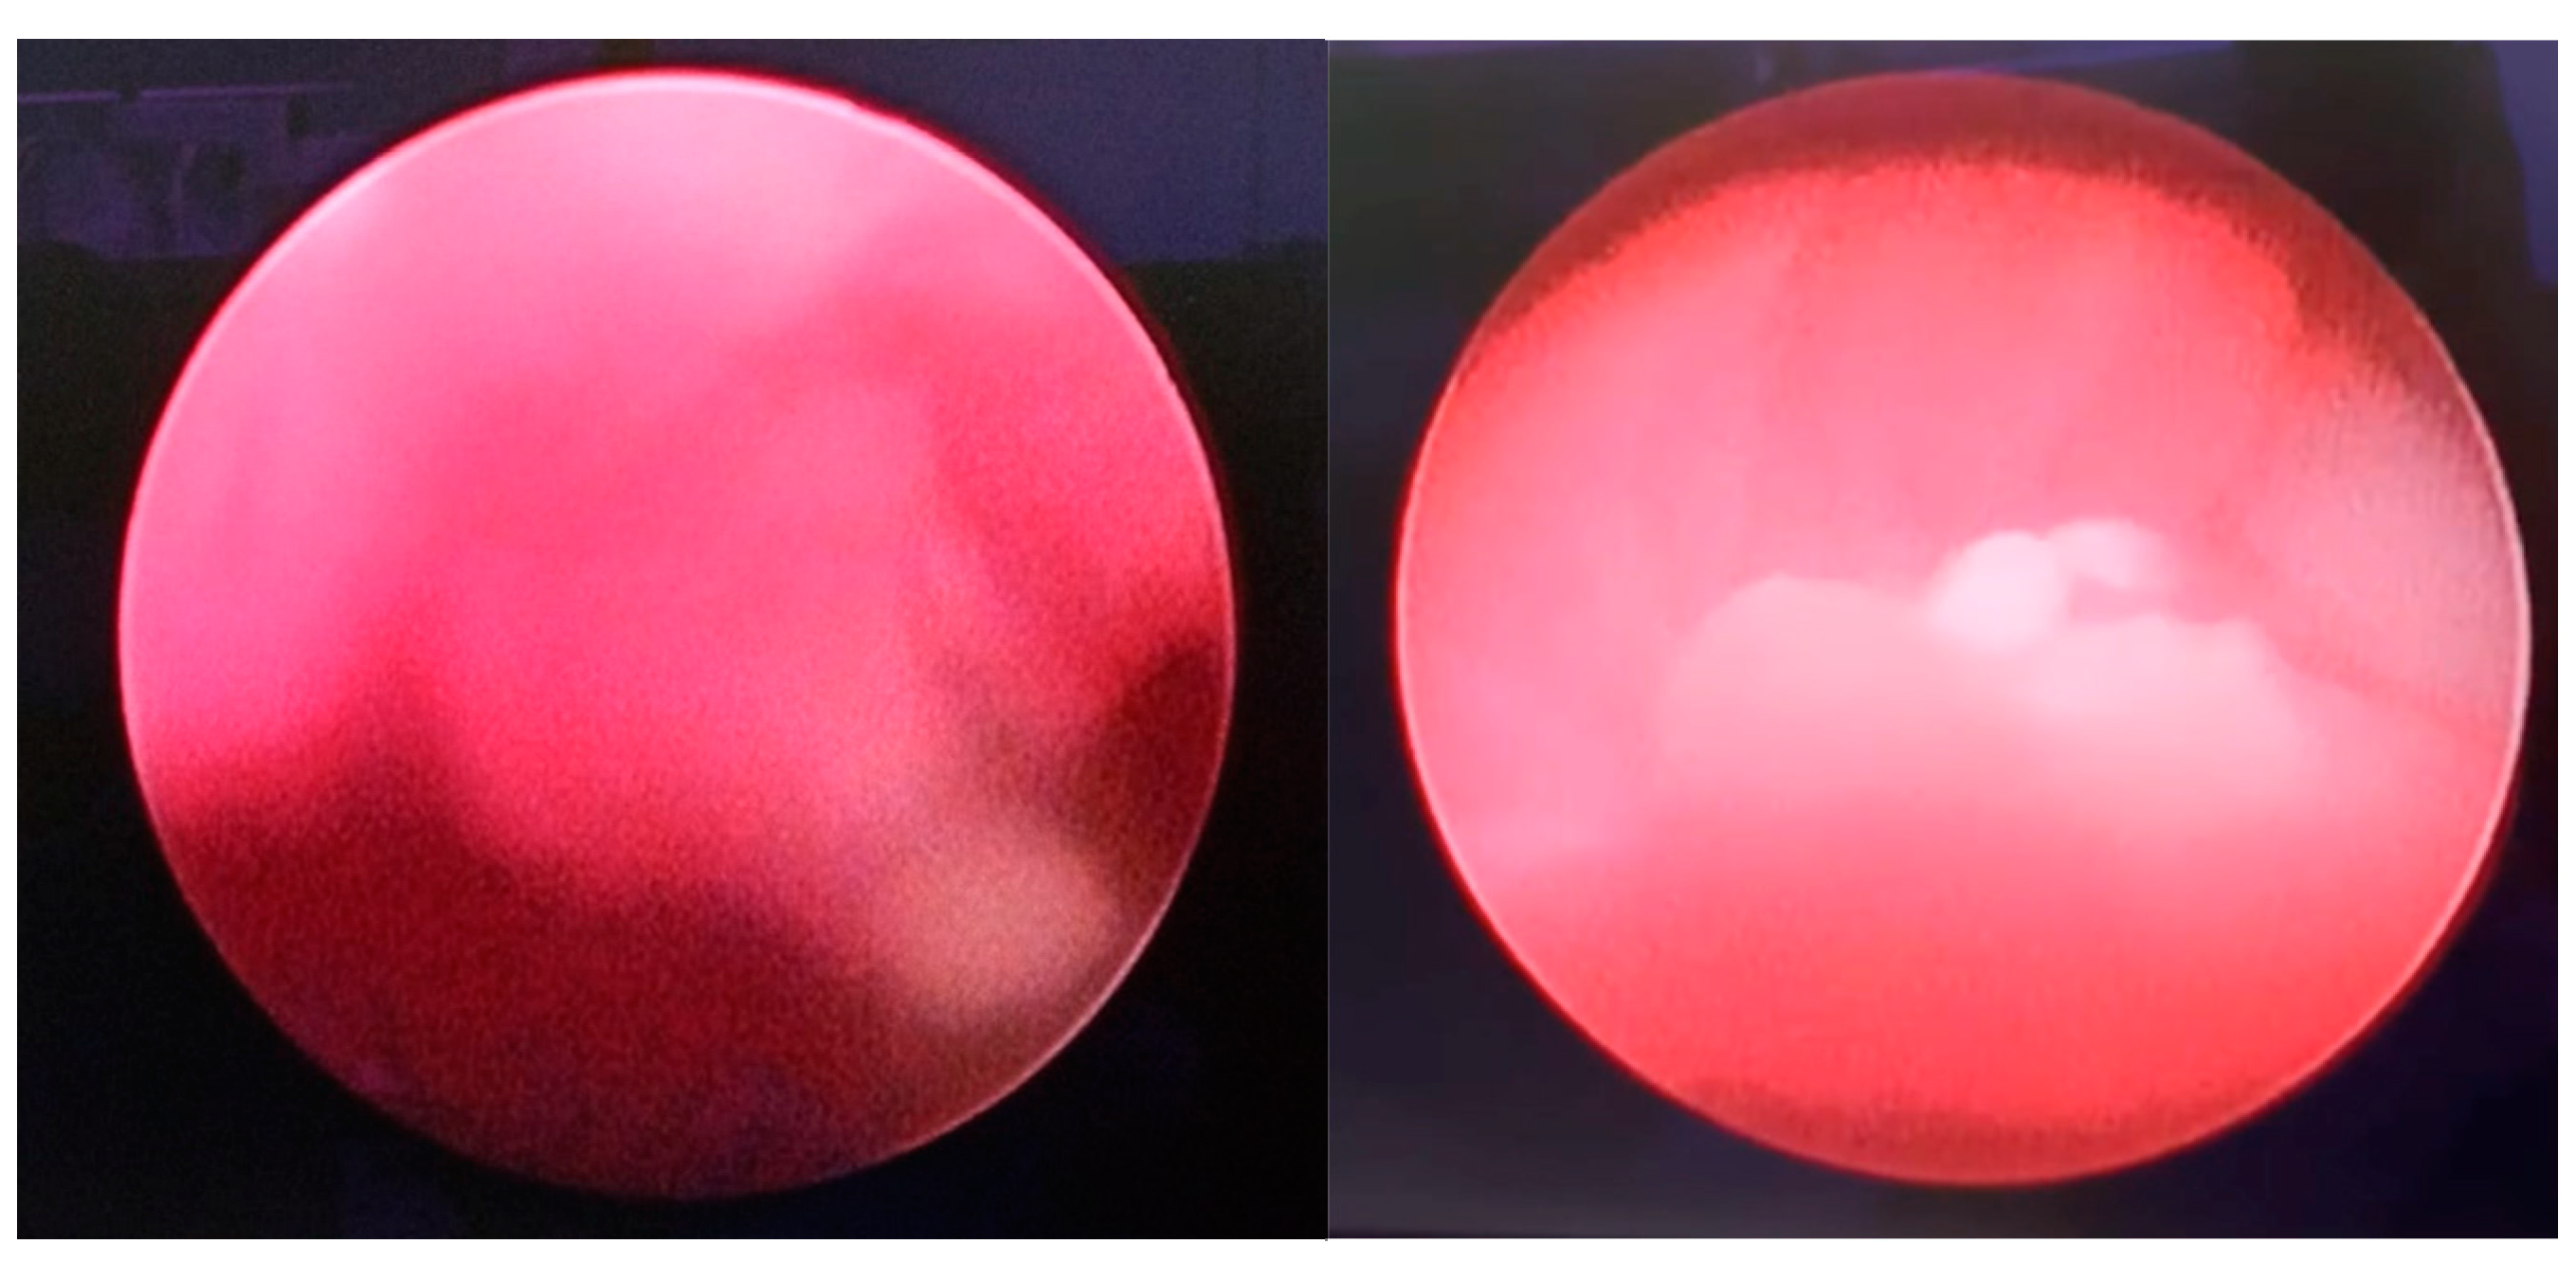

Under the direct vision, the clot was progressively fragmented with the aid of the cystoscope, compressing the clot against the neobladder wall and weakening it. The vacuum effect of the 60 ml syringe permitted a progressive clot reduction in smaller fragments, which were progressively evacuated (Figure 3).

Figure 3. Intraoperative image: the use of syringe on the urethral sheath.